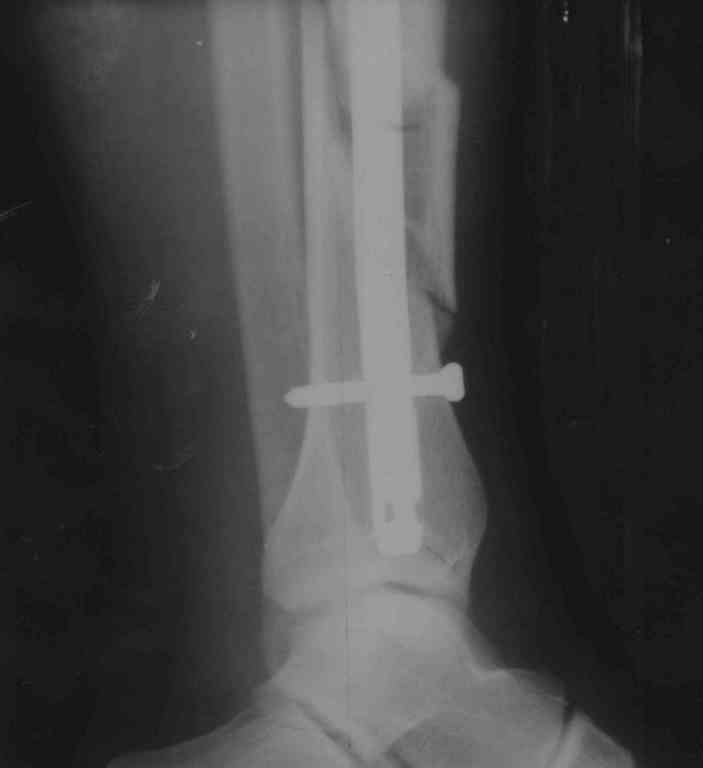

Перелом б/берцовой и малой берцовой кости в н/3 со смещением отломков |

Нужна консультация по поводу консолидации отломков б/берцовой кости после операции с остеосинтезом, все ли срастается правильно, не нужна ли повтроная операция(отломок на рис 2)по поводу отломка всавшего между большой и малой берцовой костью, или он втанет на место или раствориться,а то ощущения будто он мешает при массаже голени(болит из-за него мышца, не помешает ли при ходьбе в дальнейшем)? 1.Так же вопрос есть по ФЛК врач сказал что колено тоже повреждено-разорваны связки не полностью по словам(удалял кровь из шва под коленкой. есть твердая припухлость снизу и с внешней стороны коленного сустава,так же при лежании на поврежденной внешней стороне колена появляется боль которая пропадает при изменении положения),проведена иммобилизация коленного сустава в туторе-5 недель, после снятие подвижность в суставе около 15% от здорового коленного сустава- какие делать процедуры, чтобы потом не делать еще и опарацию на колене? очень не хочется.Мне 31 год рост 180 вес 100 , операций и заболеваний не было до этого. Зараннее спасибо за советы).

Добавляю еще снимки, после операции прошел 1 месяц, снимков сразу после операции и до нее на руки мне не дали.

По поводу перелома костей голени ничего предпринимать не нужно, все приемлемо. В сроке 2 мес. нужно посмотреть снимки и решить по нагрузке и необходимости удаления винта вверху.

Нужно этот винт удалять или нет, и когда, следует решать не сегодня, а в ходе дальнейшего наблюдения пациента. Если будут признаки активного костеобразования через 1 и 2 мес., то удалять этот винт не будет необходимости.

Нужно ли удалять весь фиксатор, и когда - тоже вопрос сегодня неактуальный. Сейчас важнее всего восстановить амплитуду движений в голеностопном суставе.